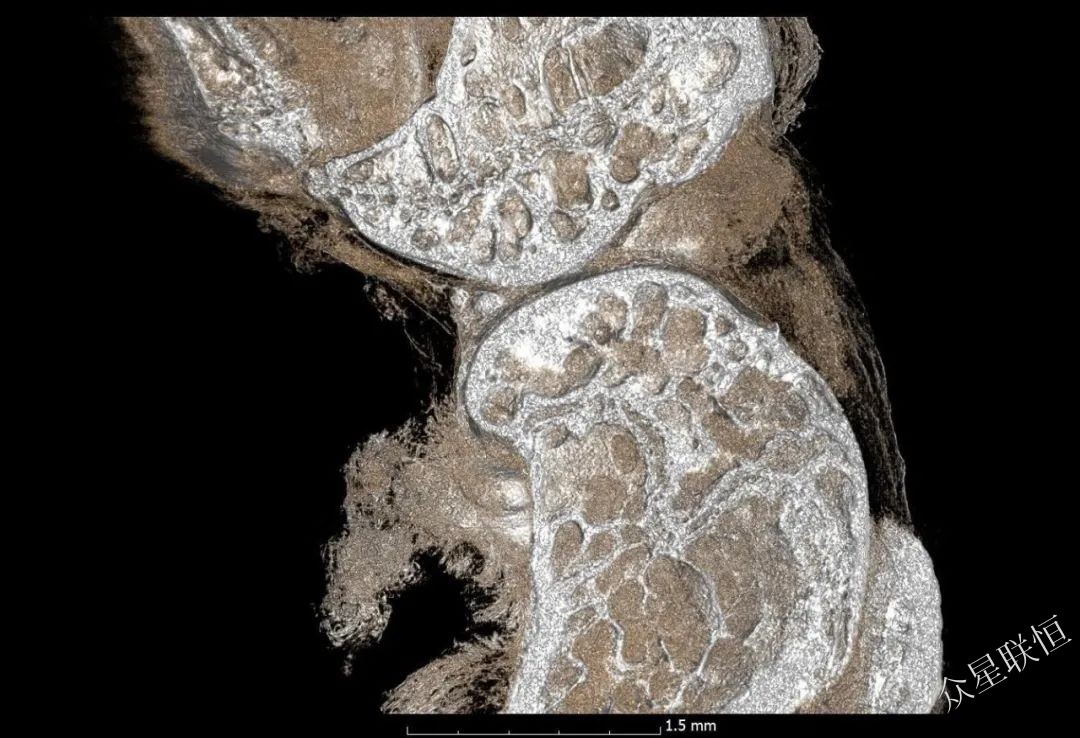

鈦植入樣品

圖像顯示了整形外科的鈦植入物,可用于不同的應(yīng)用,即檢查骨-植入物的界面。 注意,相襯改善了骨骼結(jié)構(gòu)的可視化。

不含相襯信息

含相襯信息